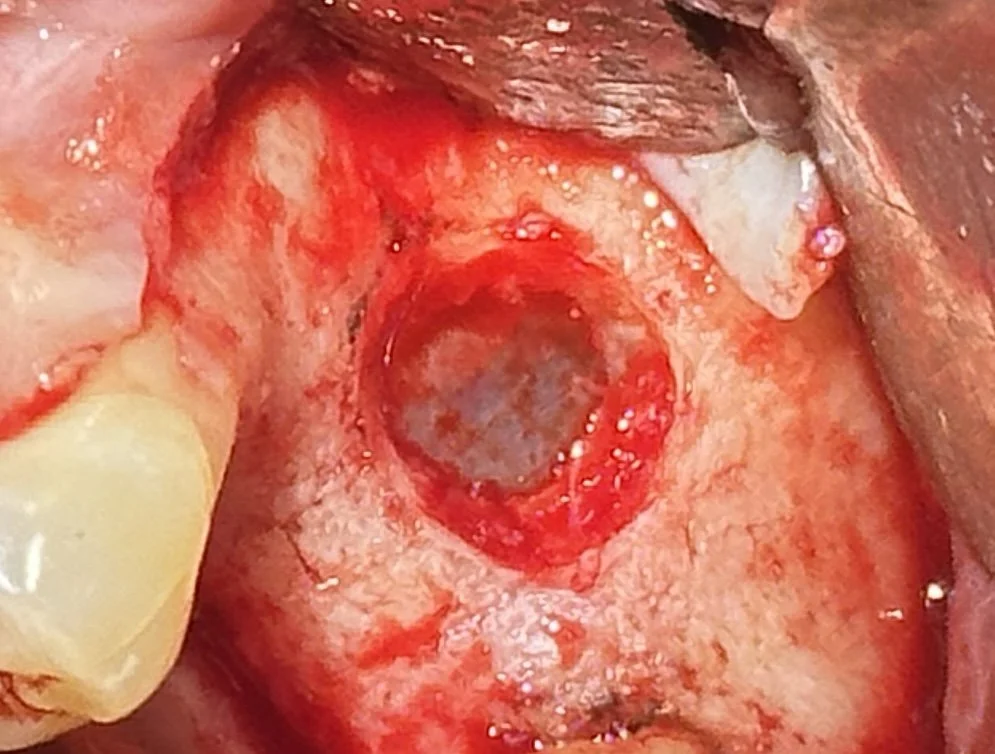

A small lateral window was created to access the maxillary sinus.

The Schneiderian Membrane lining the sinus cavity was carefully elevated to create space for graft material.

Bone grafting was performed to increase the vertical height and regenerate sufficient volume for future implant placement.

Healing progressed uneventfully, with healthy soft-tissue integration observed at follow-up.